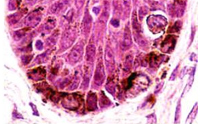

日本慶應(yīng)義塾大學(xué)教授河上裕率領(lǐng)的研究小組近日在美國在線雜志《科學(xué)公共圖書館綜合卷》上發(fā)表論文說,他們利用人體誘導(dǎo)多功能干細(xì)胞(iPS細(xì)胞),首次成功培養(yǎng)出色素細(xì)胞。

研究小組向人體皮膚細(xì)胞植入3個(gè)基因,培養(yǎng)生成誘導(dǎo)多功能干細(xì)胞,并培育出名為“胚狀體(EB)”的細(xì)胞團(tuán)塊。接著,研究人員向胚狀體植入人體制造色素細(xì)胞時(shí)所必需的成分,培育兩個(gè)月左右,結(jié)果獲得的細(xì)胞中有60%至70%是人體色素細(xì)胞。

色素細(xì)胞存在于人體皮膚等處,能夠制造黑色素,防止人體遭受紫外線傷害。色素細(xì)胞如果出現(xiàn)癌變,就會(huì)患上惡性黑色素瘤等,而出現(xiàn)皮膚變白癥狀的白癜風(fēng)和白化病以及白發(fā)等均被認(rèn)為是色素細(xì)胞減少造成的。研究小組認(rèn)為,新成果將有助于弄清上述疾病的致病原因,并且在制藥和制作人造皮膚等再生醫(yī)療中得到應(yīng)用。

Epidermal melanocytes play an important role in protecting the skin from UV rays, and their functional impairment results in pigment disorders. Additionally, melanomas are considered to arise from mutations that accumulate in melanocyte stem cells. The mechanisms underlying melanocyte differentiation and the defining characteristics of melanocyte stem cells in humans are, however, largely unknown. In the present study, we set out to generate melanocytes from human iPS cells in vitro, leading to a preliminary investigation of the mechanisms of human melanocyte differentiation. We generated iPS cell lines from human dermal fibroblasts using the Yamanaka factors (SOX2, OCT3/4, and KLF4, with or without c-MYC). These iPS cell lines were subsequently used to form embryoid bodies (EBs) and then differentiated into melanocytes via culture supplementation with Wnt3a, SCF, and ET-3. Seven weeks after inducing differentiation, pigmented cells expressing melanocyte markers such as MITF, tyrosinase, SILV, and TYRP1, were detected. Melanosomes were identified in these pigmented cells by electron microscopy, and global gene expression profiling of the pigmented cells showed a high similarity to that of human primary foreskin-derived melanocytes, suggesting the successful generation of melanocytes from iPS cells. This in vitro differentiation system should prove useful for understanding human melanocyte biology and revealing the mechanism of various pigment cell disorders, including melanoma.